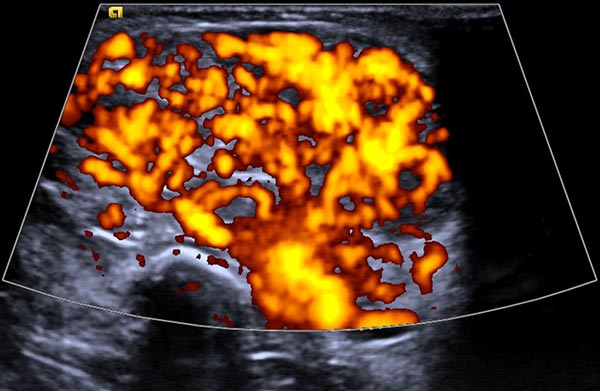

Power Doppler imaging shows strong perfusion of the mass, so that a vascular tumor is assumed. The strong blood flow is shown here in orange in the B-scan, while the direction of flow is not color-coded.

Power Doppler imaging at the end of the 8th month of life shows not only an increase in volume of the subcutaneous tumor, but also a further marked increase in perfusion (color-coded in orange).